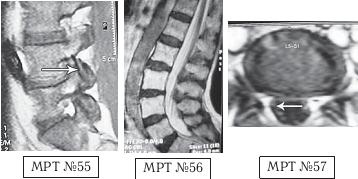

Как правило, причина вышеупомянутых болей при таких патологиях скрывается в дугоотростчатых суставах. Дело в том, что при изменении физиологического лордоза извращается «работа» и дугоотростчатых суставов. В состоянии нормы дугоотростчатые суставы имеют дугообразную форму и расположены во фронтальной, горизонтальной и сагиттальной плоскостях в среднем под углом 45о. При развитии дегенеративнодистрофического процесса в межпозвонковом диске (снижении высоты диска, возникновении сегментарной нестабильности) происходит смещение суставных поверхностей дугоотростчатых суставов по отношению друг к другу, что в свою очередь приводит к уплощению физиологического лордоза и его кифозированию (МРТ № 55) или же формированию гиперлордоза (МРТ № 56). И в том, и в другом случае данные процессы, как правило, сопровождаются сдавлением спинномозговых корешков (что вызывает соответствующие боли). Кроме того, сами дугоотростчатые суставы хорошо иннервированы, поэтому протекание патологических процессов, с участием этих суставов, сопровождается соответствующими болевыми ощущениями.

На МРТ № 55 наблюдается уплощение физиологического лордоза в поясничном отделе позвоночника. На МРТ № 56 наблюдается гиперлордоз в поясничном отделе позвоночника. На МРТ № 57 наблюдаются нарушения конгруэнтности в дугоотростчатых суставах в сегменте LV—SI (указано стрелкой) вследствие гиперлордоза.